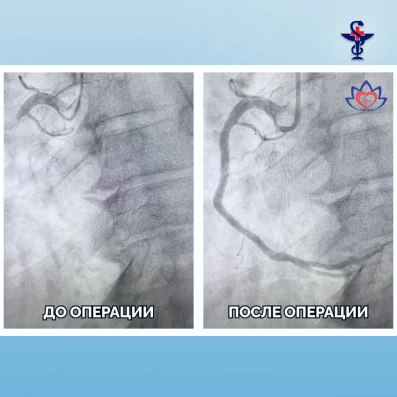

Врачи регионального сосудистого центра больницы № 3 им. С. Кирова спасли пациента с острым инфарктом миокарда.

Пациента доставили в кардиологический порт приёмного отделения больницы. После дообследования его подготовили и направили в рентген-операционную. Специалисты отделения рентгенэндоваскулярных методов диагностики и лечения оперативно восстановили кровоток в сосудах сердца, чем спасли пациента от тяжёлых осложнений.